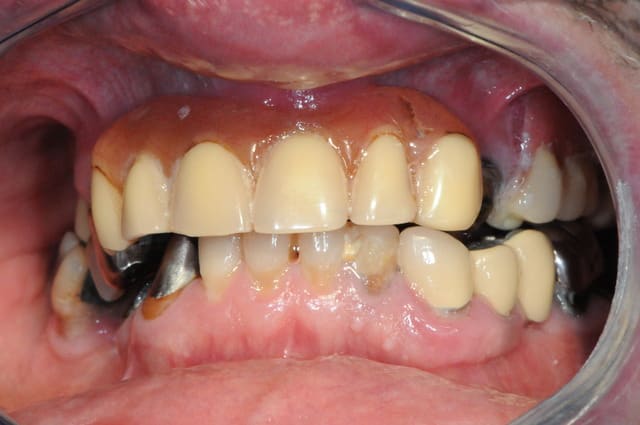

je ne voudrais pas "louper " ce cas, alors quelles idées de traitements auriez vous à me soumettre ?

bien sure il faut tout revoir, l'occlusion, la DV, la courbe occlusale, la ligne du sourire...

extraction: 14-15-23-44 et 36 (ou amputation, mais à quoi bon ?)

reprendre la courbe occlusal avec des céram sur 43-46-33-34

bridge sur implant sur 44 -46 et 35-36 (ou 35-37?)

complet haut amovible sur deux barres (donc 4 implants en haut) ou sur 4 locators (y en a qui ont déjà fait ?)

La gencive ne semble pas très belle en haut...

Au maxillaire, quels sont les avantages des implants lorsque l'on fait une prothèse amovible complète ? Essentiellement la possibilité de ne pas avoir de palais en résine.

Je pense que l'on pourrait concentrer son attention sur la mandibule, pour laquelle les solutions amovibles sont souvent moins confortables.

Le patient ayant déjà une PAP en haut, avoir un complet bien fait ne changerait pas beaucoup ses sensations et resterait d'un cout raisonnable (quitte à poser des implants pas la suite).